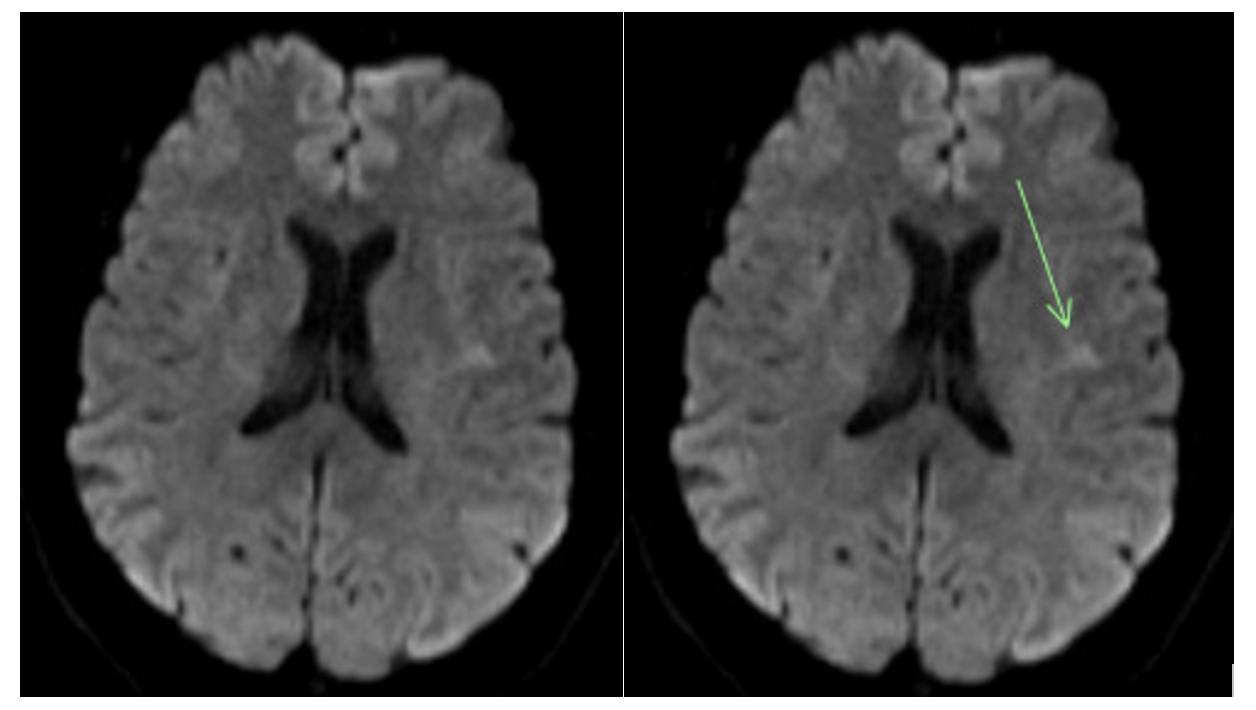

Recurrence of cardiovascular accidents (CVA) occurs frequently. Studies have demonstrated recurrence of CVA in 26% of patients within 5 years.3 This case reports a patient on antiplatelet therapy with recurrent CVA with no identifiable cause. Her stroke was classified as cryptogenic due to a lack of evidence of etiology despite repeated tests to rule out cardioembolic, aortoembolic, or atheroembolic causes. Since all the strokes occurred within the region of the left internal carotid artery (Figures 2-4), we suspect they were caused by the left internal carotid web. During DSA, the neurosurgeon noted in the operative note that the extracranial left carotid artery circulation exhibited normal caliber and course, with the exception of a very small, eccentric intimal web at the junction of the left internal carotid artery bulb and proximal cervical segment. While most carotid webs are found in the carotid bulb’s posterior margin, the carotid web in this case appeared in the anterior and distal aspect. Theoretically, a carotid web could form anywhere along the carotid artery where a thin, membrane-like shelf of tissue that extends from the wall to the lumen exists. The multitude of infarcts in the left internal carotid’s territory helps to support that this patient has a carotid web rather than a kinked or tortuous vessel, and that it has a probable role in stroke etiology.